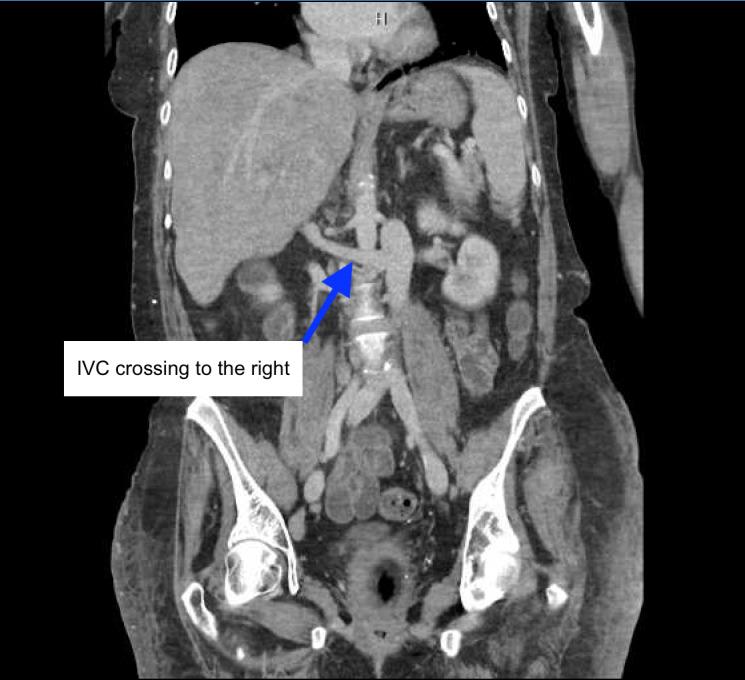

Missing Inferior Vena Cava on POCUS: A Case of Left-Sided IVC with Azygos Continuation.

The merits of utilizing point of care ultrasound (POCUS) in acutely ill patients is leading to a widespread embrace. Assessment of IVC via POCUS as part of a comprehensive multi-organ approach can help guide volume tolerance. Anatomical/developmental variations of IVC can vary widely in prevalence. As the use of POCUS expands as a diagnostic modality, it is prudent for frontline POCUS users to be cognizant of the IVC anomalies. We present a case of left sided IVC with azygous continuation discovered with POCUS that was performed to assess the volume status of the patient. This case illustrates that the awareness of different anomalies of the IVC is necessary for POCUS users to prevent misinterpretation of aberrant vessels and avoid diagnostic pitfalls.